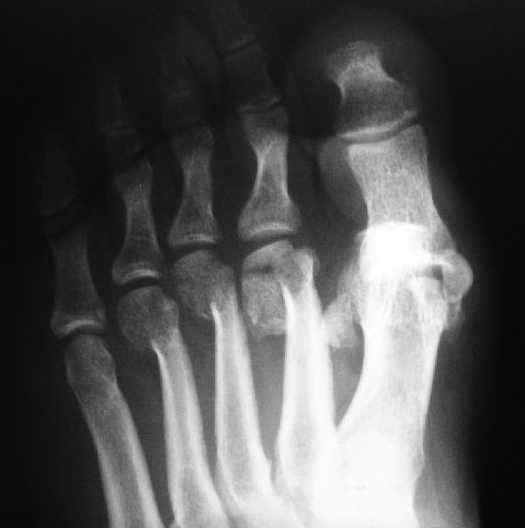

1 передний отдел стопы делается в косой, а не боковой проекции - на боковой все плюсневые кости накладываются друг на друга, и ничего не видно - это же аксиоматично! Я, например, на прямых проекциях не вижу совсем признаков перелома первой и четвертой плюсневой, и сомневаюсь в переломе третьей, боковые же совершенно неинформативны.

Как же суть проблемы видна? Человек говорит о переломе первой (то есть речь идет о переломо-вывихе?), второй, третьей и четвертой плюсневых костей, а я вижу только перелом второй. мне кажется, что проблема в таком случае будет чуть-чуть другая. Кстати, сколько переломов насчитали на этих снимках Вы?

Однозначно-переломы 1,2,3,4 плюсневых костей.

Уважаемый Давид! По наличию переломов можете не сомневаться, возможно проблема в качестве передачи изображения, но на сегодняшнюю тактику не влияет.

Имеем - без малого двухмесячные переломовывихи перeднего отдела стопы , больной в отделении 20 дней, доктор думает, что ему делать:

1 полное смещение второй плюсневой, которое НАВЕРНЯКА приведет к появлению натоптыша и невозможности нагружать передний отдел стопы - всеми участниками просто игнорируется.

2 когда несколько участников высказали свое сомнение в наличии переломов 3-4 плюсневой - автор просто сказал - 'поверьте мне на слово, они поломаны'

3 На мой вопрос - где же перелом певрой плюсневой ( согласитесь, наличие такого повреждения напрочь меняет тактику лечения) - ответа не последовало никакого

Не знаю, что за проблема, но я на своем мониторе переломы отлично вижу.

Та же проблема - по крайней мере на снимке в аппарате (фас) отчетливо видно перелом ее головки.